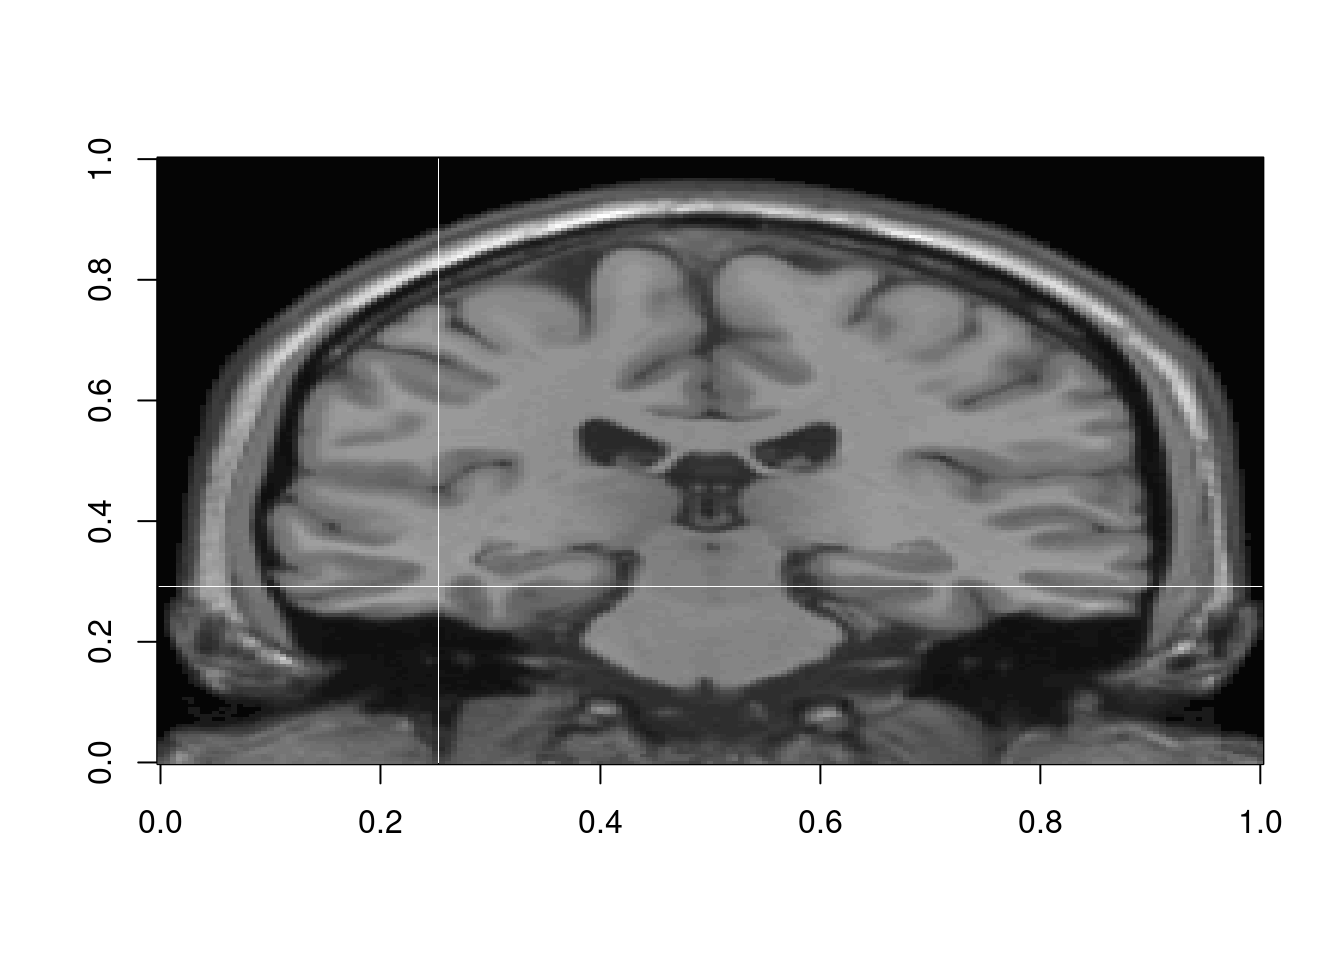

Plano coronal ou plano frontal é um dos tipos de planos anatômicos, dividindo o corpo com cortes verticais e perpendiculares ao plano mediano. Assim é possível definir a parte ventral/anterior (frente) da parte dorsal/posterior (costas).

Para visualizar no ângulo sagital:

Para visualizar no coronal:

#Imagem Coronal na fatia y=100

image(volume[,100,,1], col = gray((1:50)/50))

Nota: Não é possível identificar facilmente se o lado é esquerdo ou direito. Depende se a notação da imagem coletada é radiológica ou neurológica.